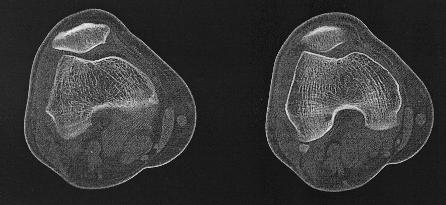

CT van het skelet

Een Ct-scan van het skelet wordt uitgevoerd wanner er een verdere evaluatie nodigs van een lestel dat gezien is op een klasieke foto. Denk aan fracturen, luxaties e.d., maar ook aan metastasen, arthrose,...Zo kan het bijvoorbeeld zijn dat een letsle niet duidelijk genoeg voorkomt op de foto's endat er dus twijfel bestaat. Maar ook kan het zijn dat een CT-scan noodzaklijk is om een duidelijk beeld te verkrijgen van een uitgebreide fractuur, om verder behandeling te bepalen.

Dankzij de moderne computertechnieken is het niet allen mogelijk om axiale beelden te maken. (lees schijfjes dwars op het lichaam) Maar ook om die beelden te reconstrueren tot een 3D-model. Dit geeft vaak een duidelijk beeld van het bot, en zijn letsel.